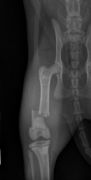

radiographie thorax chatenclouage centro médullaire fémurfracture fémur

Fracture

Nous disposons d'un équipement de radiologie numérique.

Les radiographies sont d'un atout majeur dans le diagnostic de nombreuses pathologies (fractures, problèmes respiratoires, troubles digestifs ...).